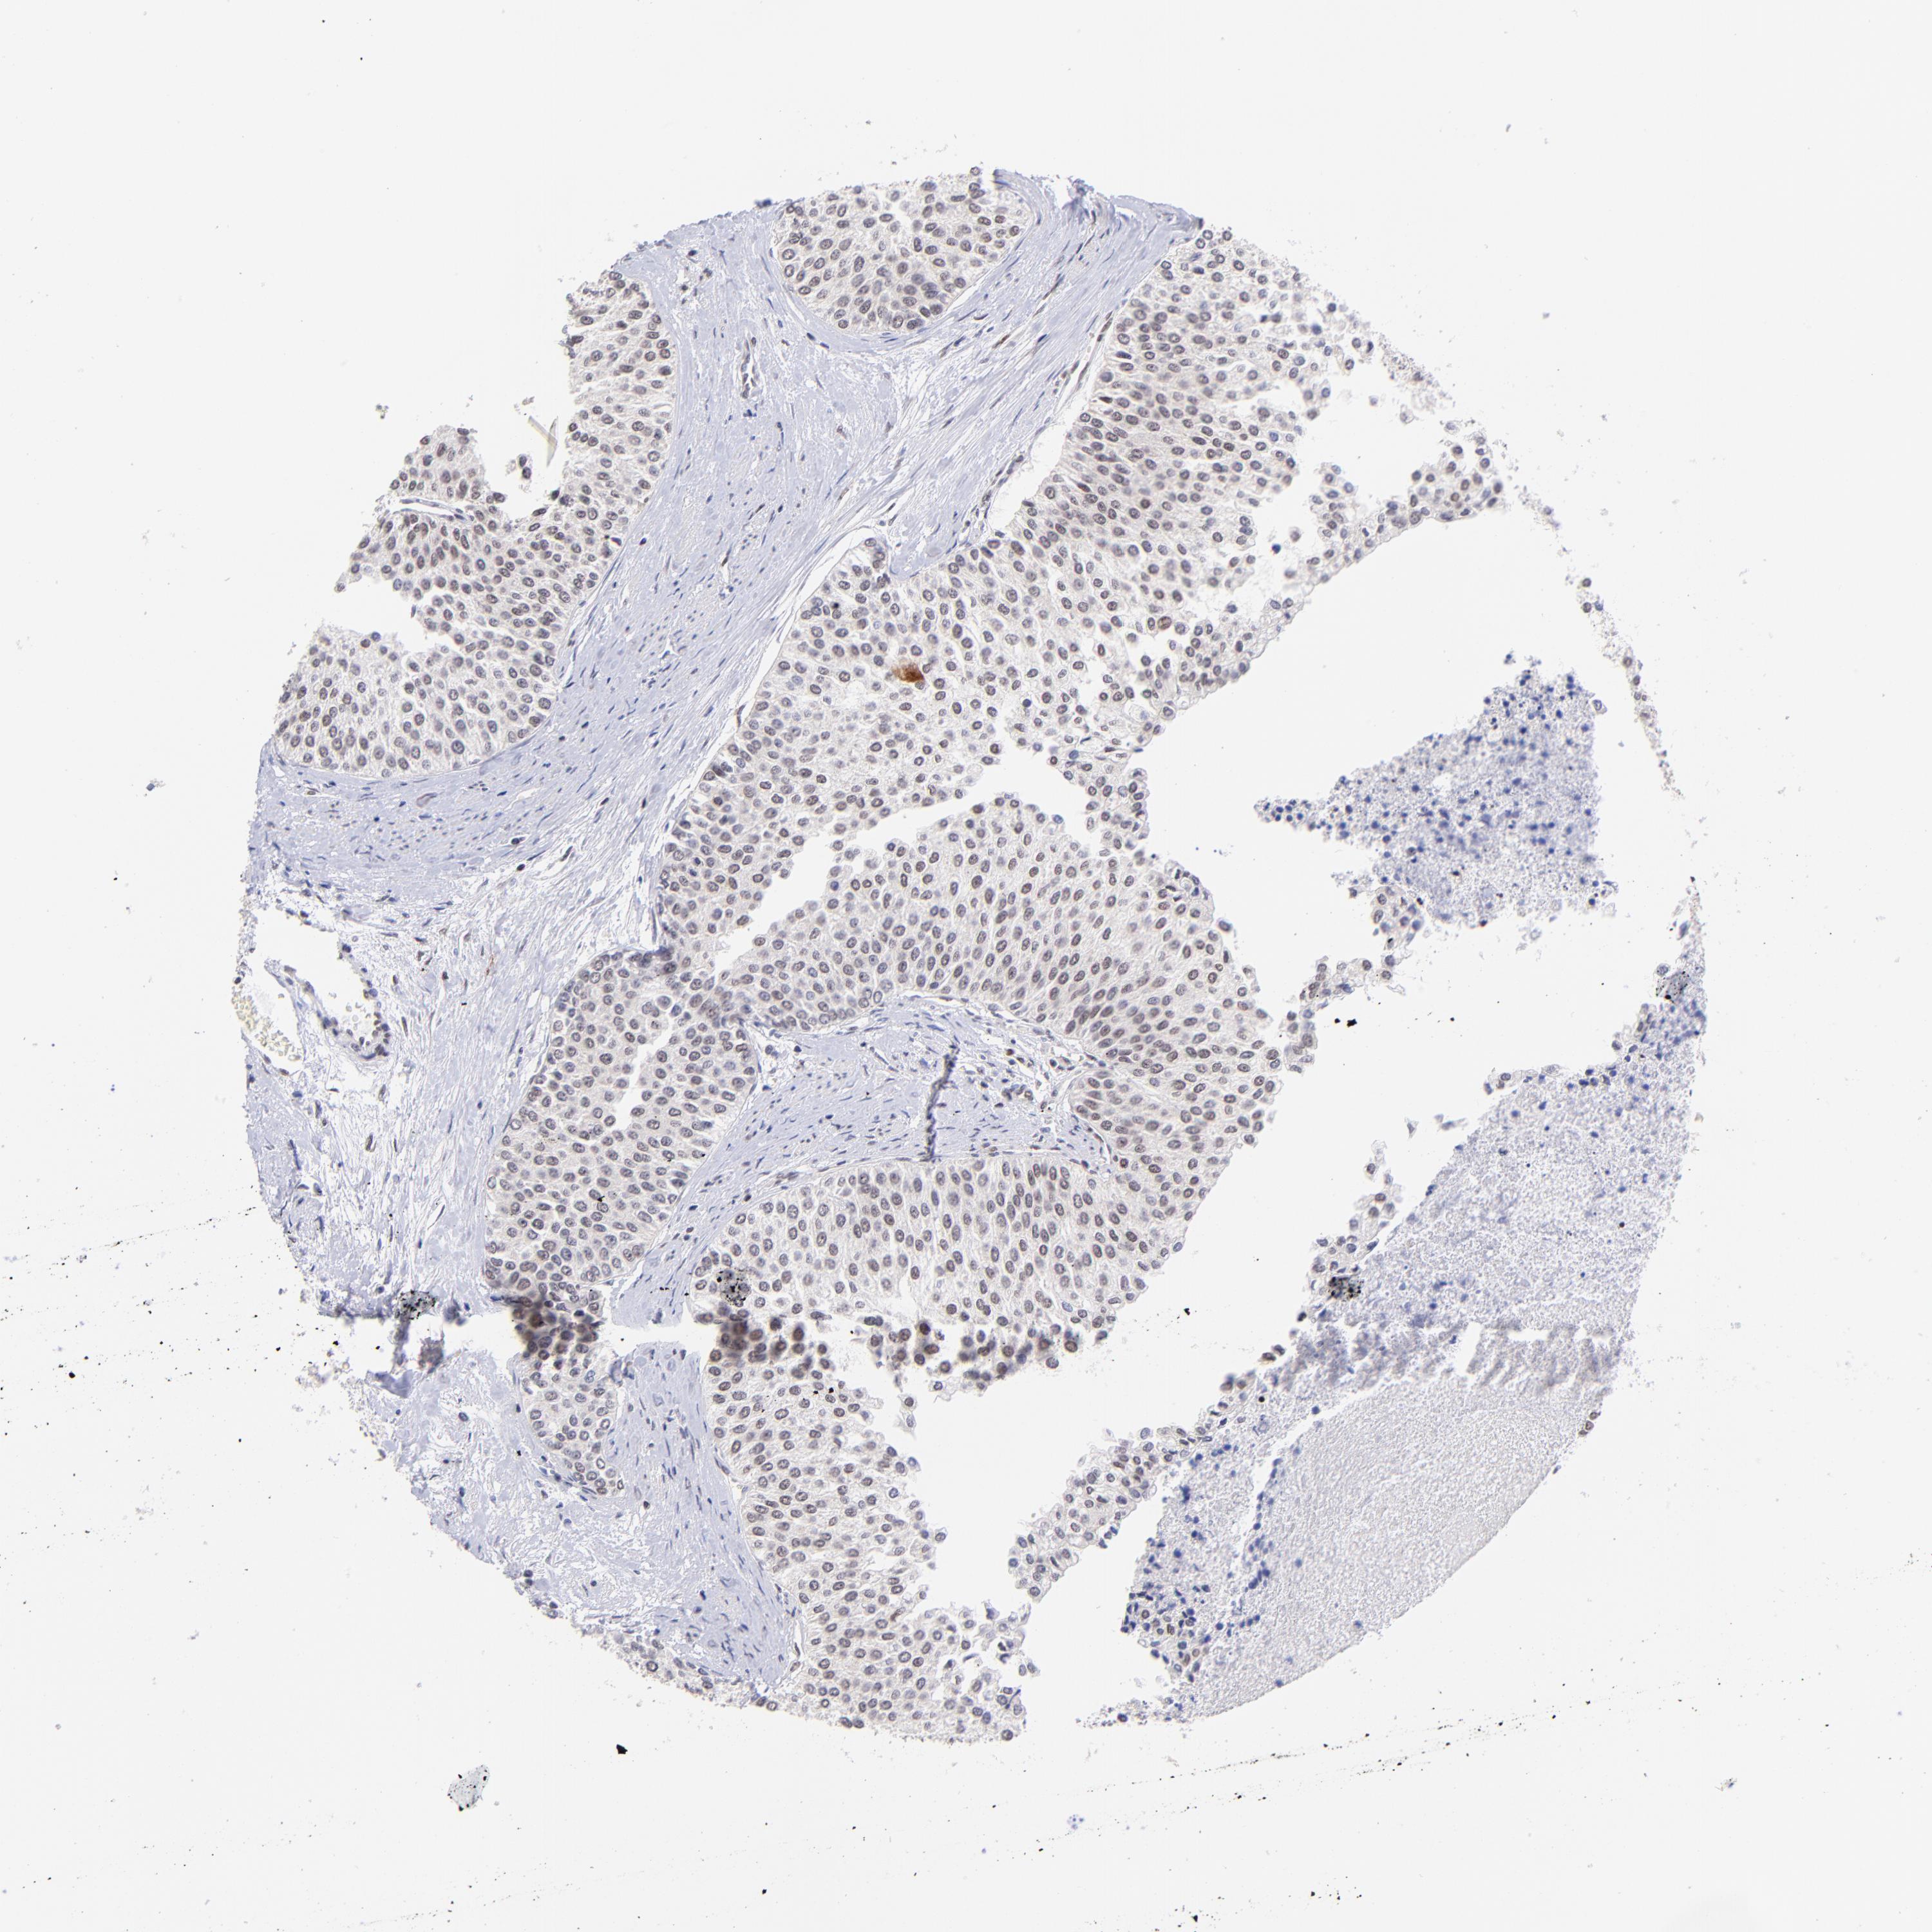

UROTHELIAL CANCER - Protein expressioni

A mouse-over function shows sample information and annotation data. Click on an image to view it in a full screen mode. Samples can be filtered based on level of antibody staining by selecting one or several of the following categories: high, medium, low and not detected. The assay and annotation is described here.

Note that samples used for immunohistochemistry by the Human Protein Atlas do not correspond to samples in the TCGA dataset.

Antibody stainingi

Antibody staining in the annotated cell types in the current human tissue is reported as not detected, low, medium, or high, based on conventional immunohistochemistry profiling in selected tissues. This score is based on the combination of the staining intensity and fraction of stained cells.

Each image is clickable and will lead to virtual microscopy that enables deeper exploration of all samples and also displays staining intensity scores, fraction scores and subcellular localization as well as patient and tissue information for each sample.

Antibody HPA003111

Staining

High

Medium

Low

Not detected

Intensity

Strong

Moderate

Weak

Negative

Quantity

>75%

75%-25%

<25%

None

Location

Nuclear

Cytoplasmic/membranous

Cytoplasmic/membranous,nuclear

Urothelial carcinoma, High grade

Urothelial carcinoma, Low grade